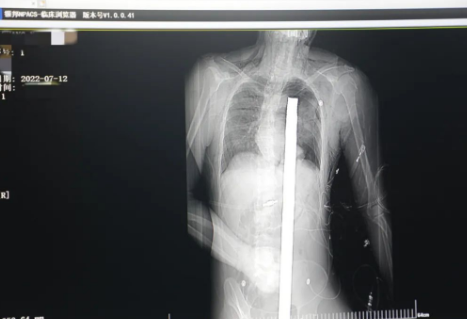

突發(fā)!太疼了,1.2米長的螺紋鋼從男子會陰部垂直穿入胸腔......7月12日下午16時10分,西安一處工地的一名26歲工友,不慎從10多米的高空墜落,不幸的是工地上一根直徑3厘米的螺紋鋼從男子會陰部垂直穿入體內(nèi),工地上的工友們小心翼翼地將連……